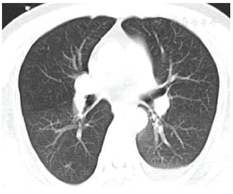

辅助检查:血常规:WBC 25.7×109/L,NE 60.2%,PLT 49×109/L。肝肾功能:ALT 360 U/L,AST 175 U/L,CREA 207 μmol/L。凝血:PT 16.7 s,APTT 74.7 s。心电图:窦性心动过速。完善胸部CT检查:未见明显异常(图1)。腹部CT:肾脏形态不规则,体积局部增大,周围渗出边缘毛糙(图2)。